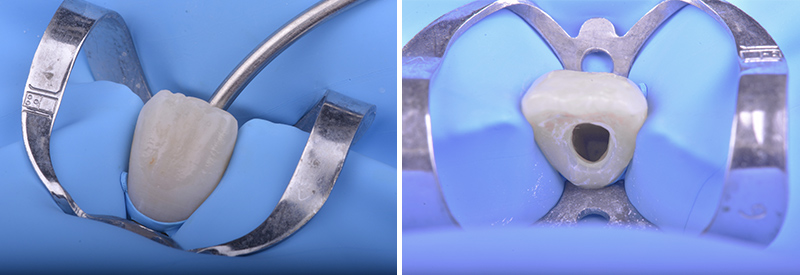

Fig. 03 et 04 : isolation unitaire à l’aide d’un crampon incisif et vue clinique de la cavité d’accès.

Après mise en place du champ opératoire la cavité d’accès est réalisée. Cette dernière de taille légèrement plus importante qu’une cavité standard doit s’adapter à la situation clinique et à la nécessité de pouvoir réaliser avec précision le bouchon apical.